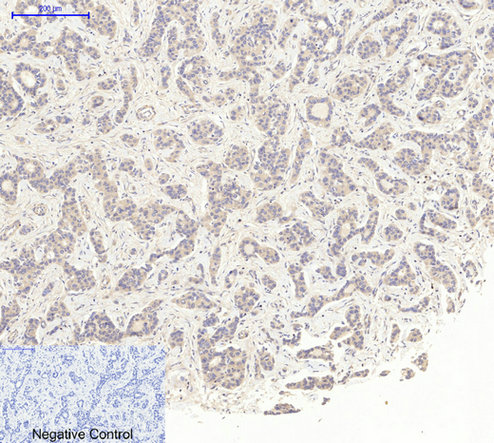

Immunohistochemical analysis of paraffin-embedded Human-uterus-cancer tissue. 1,Actin β Polyclonal Antibody was diluted at 1:200(4°C,overnight). 2, Sodium citrate pH 6.0 was used for antibody retrieval(>98°C,20min). 3,Secondary antibody was diluted at 1:200(room tempeRature, 30min). Negative control was used by secondary antibody only. |